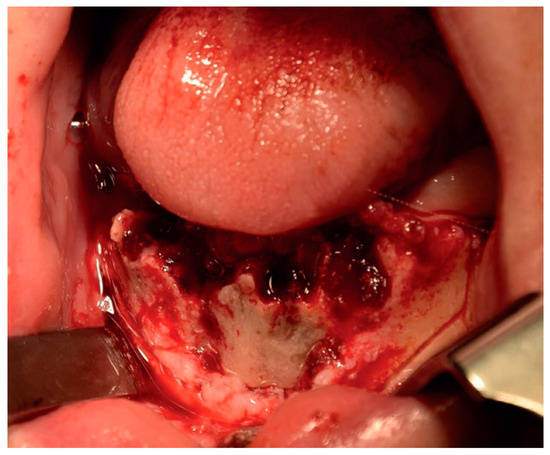

2.2. Clinical Findings

2.5. Therapeutic Intervention

3. Results